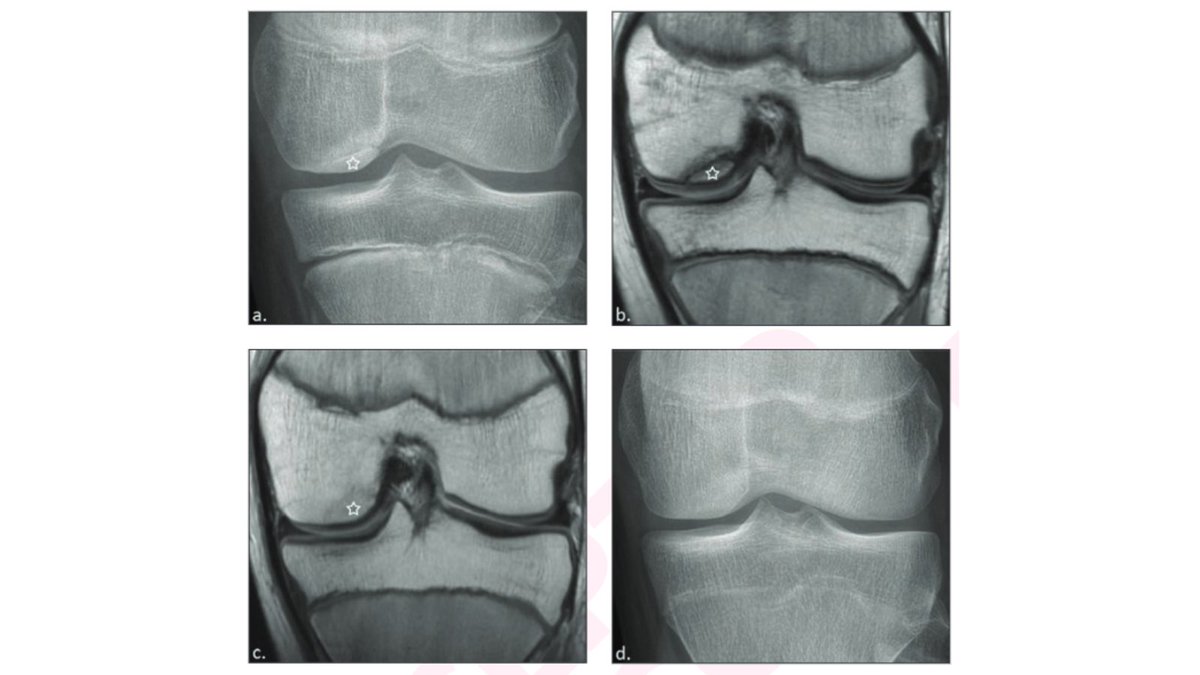

grateful for this opportunity to share our collaborative research @choporthoresrch @CHOP_Research @CHOPRadiology OCD #knee in #Pediatrics #MRI #treatment #arthroscopy Thank you @arosenkrantzmd, @therealjonadill, @AJR_Radiology

@arosenkrantzmd

Andrew Rosenkrantz

1 year

New @AJR_Radiology Accepted Manuscript: "Osteochondritis Dissecans of the Medial Femoral Condyle: MRI Findings of Instability" By Dr @nguyen_jie & team @CHOPRadiology https://t.co/sLKAfMCb4j